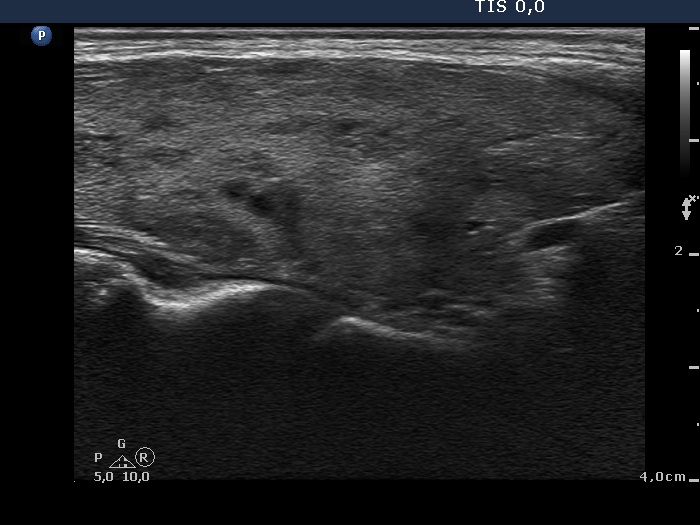

Consecutively operated patients with autoimmune thyroid disease - case 18 (1741) (ultrasonographic picture 3)

Lower part of the right lobe, longitudinal view.